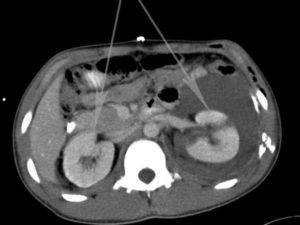

КТ – компьютерная томография, принцип которой схож с рентгеновским аппаратом. В ходе обследования проводится сканирование органа с применением рентгеновских лучей, после чего результаты появляются на экране монитора.

Наиболее известным способом диагностики является КТ или компьютерная томография. Она разработана на основе рентгеновского излучения, которое давно и широко применяется в медицине. Томограф представляет собой огромный аппарат, производящий лучи рентгена высокой мощности.

С помощью специальных датчиков они веерообразно проецируются на участки тела, требующие изучения и обследования. Они хорошо просвечивают плотные ткани, кость, хрящевые соединения и суставы.

КТ и МРТ почек — это высокоточные визуализационные методы исследования. КТ почек — это рентгенологический метод исследования, методика которого базируется на возможности объемной визуализации тканей и проектировании данных на экран компьютера. КТ почек бывает без использования контраста и с использованием йодсодержащего контраста для лучшей визуализации сосудов и тканей.

К примеру, КТ почек позволяет визуализировать кальцинаты и солевые отложения, что делает этот метод более подходящим для диагностики мочекаменной болезни и камней в почках.